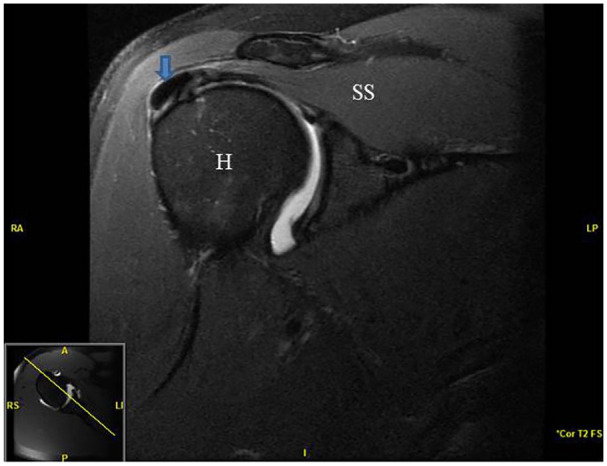

In addition to the history and physical examination, all patients underwent an x-ray (AP external rotation, Internal Grashey, Axillary and scapular Y views) and MRI with or without intra-articular contrast dye to confirm the diagnosis of calcific tendinopathy of the rotator cuff and to exclude other pathology such as full thickness rotator cuff tearing. Figure 1 demonstrates an MRI showing a calcific deposit in the supraspinatus tendon from one the patients from the current case series. Finally, all patients underwent a diagnostic ultrasound examination to further characterize the calcific deposit and determine procedure planning. Diagnostic ultrasound is commonly used to add further value and even replace the MRI scan by noting factors such as subtle rotator cuff tears, focal tendinosis, suggested hardness of the calcific deposit based on echogenicity and shadowing.23-25 Hardness of the calcium deposit is presented in Table 1. Figure 2 presents an ultrasound image demonstrating calcific deposit in the supraspinatus tendon.

Figure 1.

Pre-procedure MRI image of a patient with right shoulder calcific tendinopathy of the supraspinatus. Arrow signifies calcium deposit in the supraspinatus tendon.

Abbreviations: H, humeral head; SS, supraspinatus.